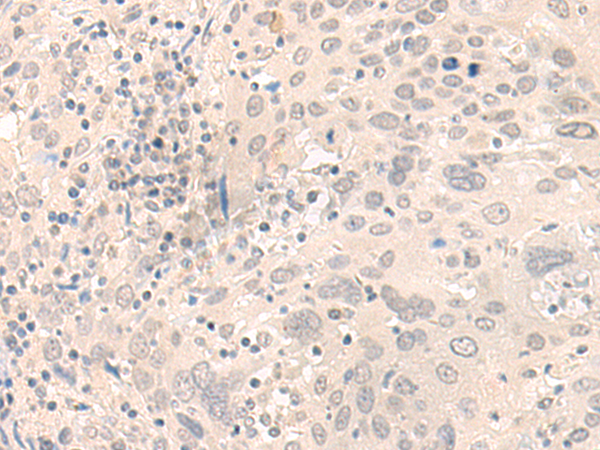

分类: 科研抗体货号: P09795别名: MCAK; CT139; KNSL6应用: IHC反应种属: Human, Mouse, Rat